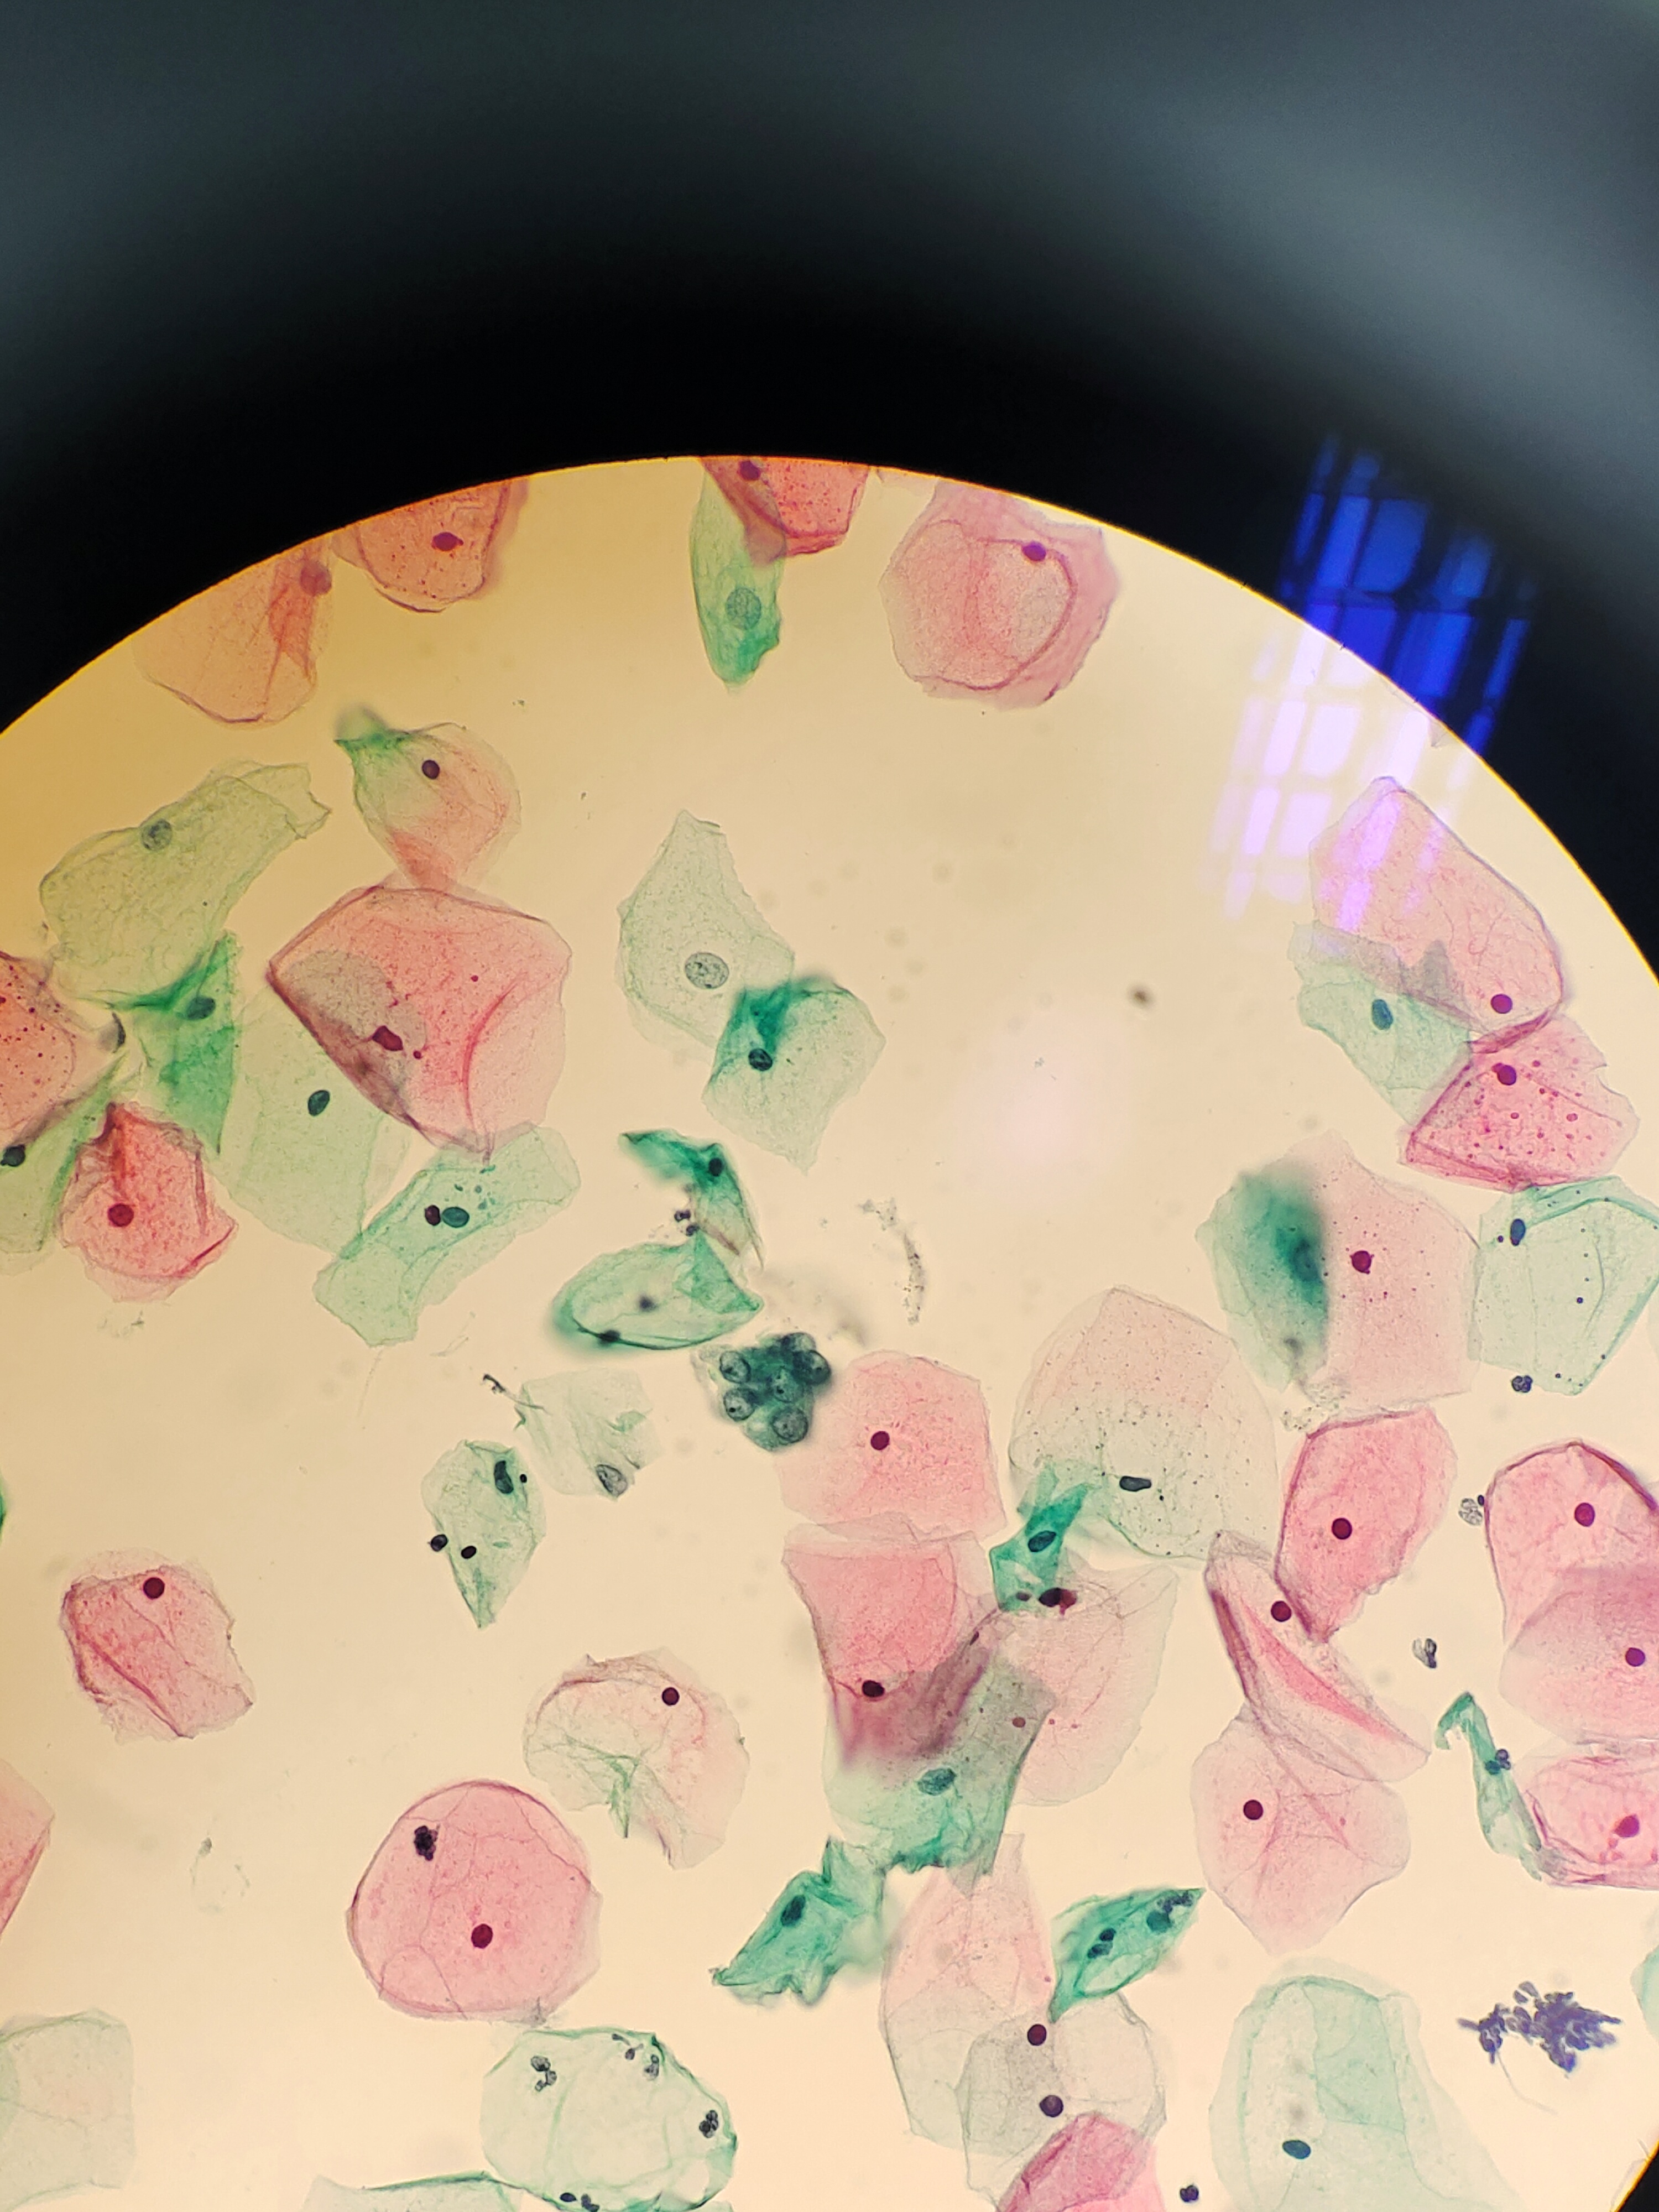

月经过后7天,下腹痛伴阴道少量血性分泌物,宫颈肥大、糜烂、触血。HPV阴性。老师们,成团细胞,有些核大,有事吗?

宫颈

液基

巴氏

图2

NILM